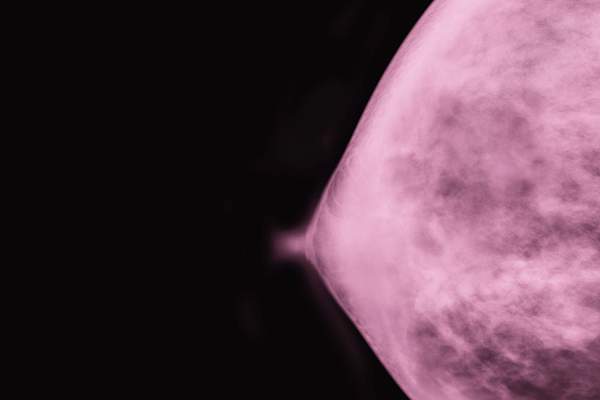

林博士说,虽然大多数的这些乳头问题可能没什么大不了的,他们可以是一个潜在的问题的迹象,如果他们坚持。如有疑问,请参阅您的文档 - 我们谈论你的乳房,毕竟。“特别是如果这些变化迅速变得更糟了物质几天或几周或抗生素,并给予似乎不提高其他药物治疗的,那么你可能要问对乳腺癌的评价,”她说。这可能包括乳房X光检查以及其他场次。

积极主动地了解乳腺癌

如果你超过40岁,美国癌症协会推荐得到乳房X线照片,每年(或每两年一次,如果你是55岁以上)。您可以选择开始甚至更早,如果乳腺癌在您的家庭中运行。“每当有人是有一个新的乳房症状,特别是如果它似乎是持续的,它从来没有一个坏主意,打电话给你的初级保健医生,” Dominici博士说。追赶乳腺癌早期大大提高您的击败它的可能性。底线:你知道你的身体最好的。如果有什么感觉了,相信自己的直觉。